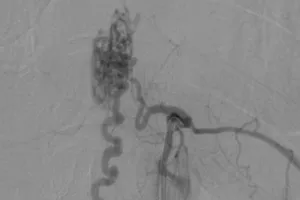

Chớ xem thường 2 chân đột ngột yếu kèm đau lưng